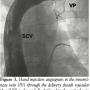

to deliver closure devices for patent ductus arteriosus. The design of this sheath with 180° curve was ideal to achieve the desired position. Through femoral vein approach, with a right coronary Judkins catheter and the aid of a 0.035″x 260 cm Wholey floppy wire (Mallinckrodt Inc.) we positioned the catheter in the VV and exchanged the guidewire for an extra stiff Amplatz (Cook Medical Inc.). The delivery sheath was advanced just above the pulmonary vein (Figure 1). Dilator and extra stiff wire were retrieved under sealed water to avoid air embolism considering that all this venous system was connected to the LA. The vascular plug was advanced until the tip of the sheath. Deployment of the device was performed by retracting the sheath over the delivery wire. Levophase angiogram in the left pulmonary artery was recorded to reveal the exact position and permeability of the pulmonary veins. VV was completely occluded, and pulmonary venous blood flow was directed towards LA (Figure 2). With the device still attached, an angiogram through the delivery sheath was performed to rule out obstruction of the IV (Figure 3). After release, manual contrast injection through a venous access of the left superior limb showed no obstruction of the systemic venous flow (Figure 4). Patient was discharged from the hospital without events 24 H after intervention and antiplatelet therapy with aspirin was indicated for 6 months.